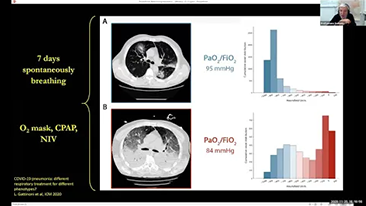

Wyb├│r odpowiedniego ustawienia respiratora do leczenia pacjent├│w z chorob? dr├│g oddechowych to bardzo wa?na kwestia. Poniewa? zadanie polegaj?ce na okre?leniu parametr├│w sprz?tu do wentylacji jest wykonywane w ca?o?ci przez lekarza, wiedza i do?wiadczenie lekarzy w wyborze tych parametr├│w ma bezpo?redni wp?yw na dok?adno?? podejmowanych decyzji. Paradygmat opieki ze wsparciem dla pacjent├│w zmieni? si? znacz?co w ci?gu ostatnich 20 lat. Na podstawie analiz potrzeb klinicznych opracowano r├│?ne tryby wentylacji i narz?dzia wspomagaj?ce podejmowanie decyzji, aby pom├│c opiekunom zwi?kszy? efektywno?? i zminimalizowa? ryzyko b??d├│w w podejmowaniu decyzji klinicznych.